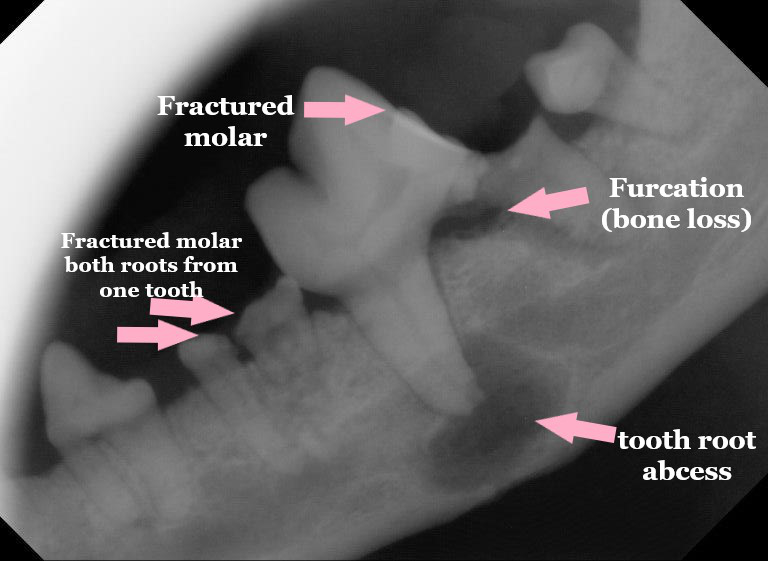

When your pet’s behaviour changes or you notice your pet is in distress, you need some quick answers. We offer full service on-site diagnostics. We have up to date technology with on-site testing, enabling quick and accurate results for patient care. Our in-house lab includes urine and blood analyzers with some of the newest AI technology. We also offer digital x-rays (including dental) and ultrasound.

In-house diagnostics